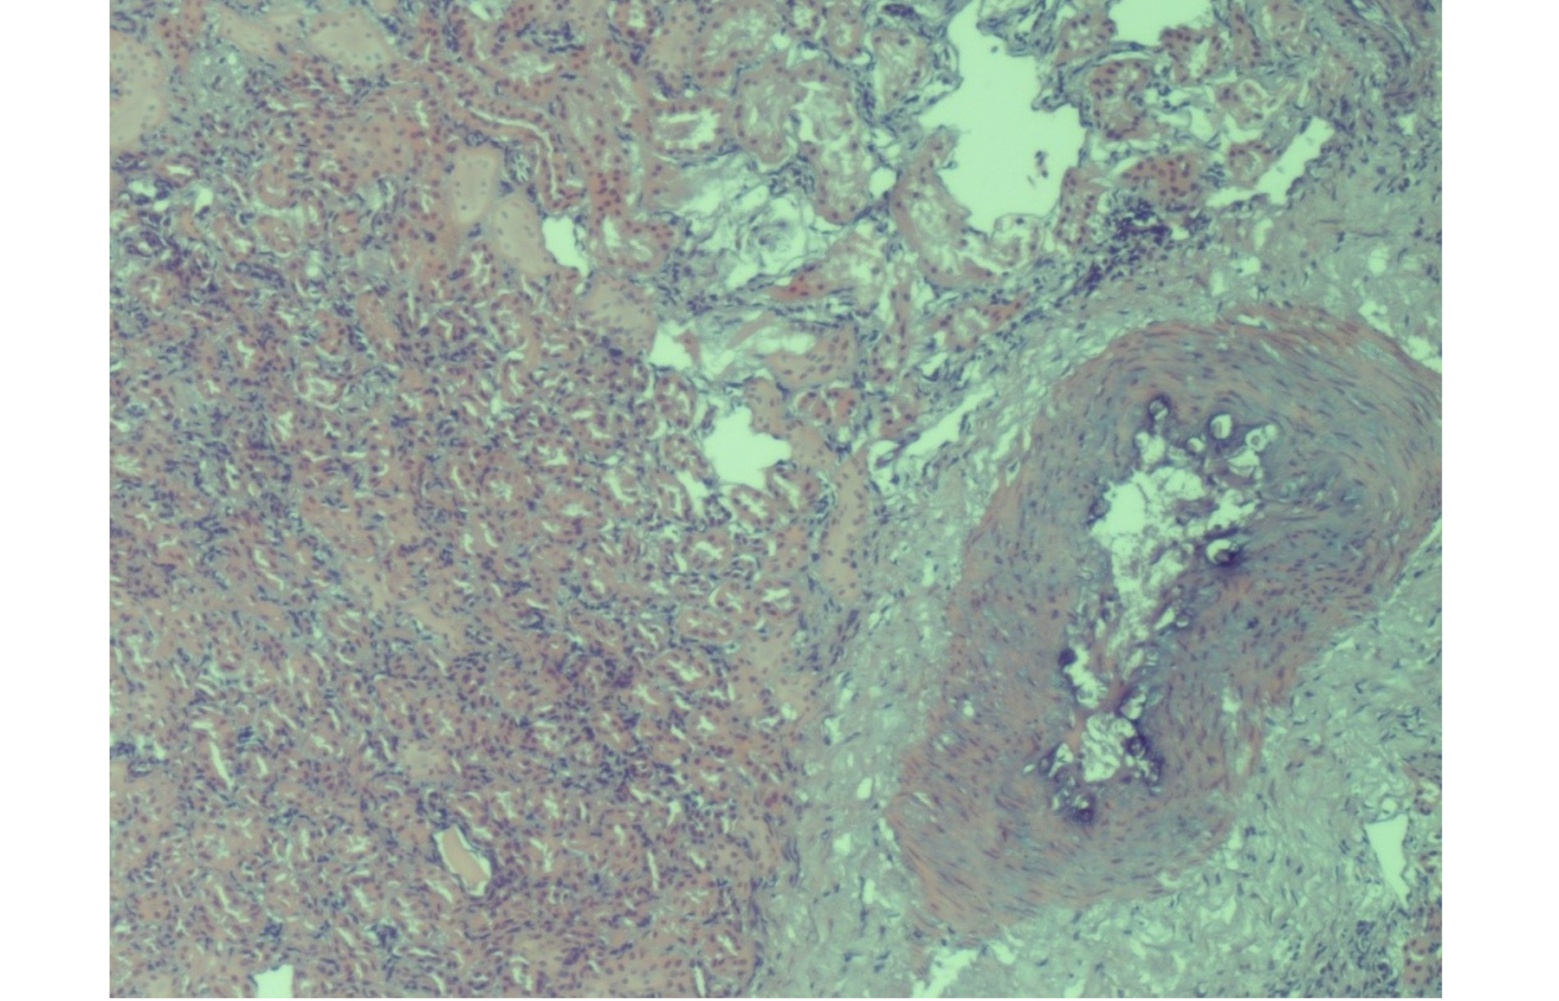

Histological lesions were observed in 19 kidney samples, all exclusively from group 1, with cadmium concentrations > 5.72 mg/kg w/w and from animals aged between 50 and 60 months. These samples exhibited the presence of neutrophils within the glomerular tufts and varying degrees of mesangial cell proliferation. Features consistent with obstruction typical of acute nephritic syndrome—progressing toward chronicity—were also observed. The glomerular capillary lumens appeared reduced, thereby compromising glomerular filtration (Figure 1).

Furthermore, evaluation of the histological kidney sections revealed marked proliferation of Bowman’s capsule cells, localized to part of the capsule’s circumference, forming the characteristic crescent-shaped structures. Tubulonephrosis and glomerulopathy were also evident (Figure 2).The progressive proliferation of the crescent led to obliteration of the glomerular tuft, resulting in irreversible destruction of the glomerulus and subsequent nephron atrophy (Figure 3). Additionally, perivascular sclerosis was observed in small- and medium-calibre arterial vessels (Figure 4).

Figure. 1. Kidney: obstruction of glomerular capillary lumina. HE (Hematoxilin Eosin) x 40.

Figure. 2. Kidney: great proliferation of Bowman’s capsule cells. Tubulonephrosis and glomerulopathy HE (Hematoxilin Eosin) x 20.

Figure. 3. Kidney: nephron atrophy and progressive tubule interstitial glomerular-nephritis. HE (Hematoxilin Eosin) x 20.

Figure. 4. Kidney: perivascular sclerosis in the small and medium-calibre arterial vessels. HE (Hematoxilin Eosin) x 10.